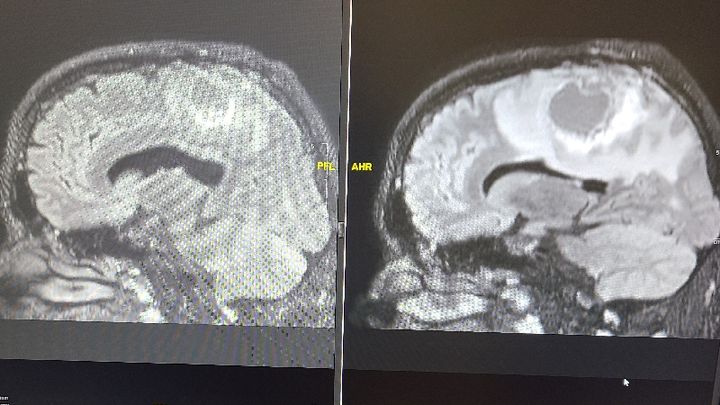

Ethan was diagnosed with an aggressive form of glioblastoma stage 4 brain cancer in June of 2020 he is done really well over the past year and a 1/2 with all his MRI scans being clear until his scan on October 7th 2021 when there was something alarming on his scan He was referred back to his neurosurgeon at Harborview where we are awaiting an appointment To find out the next steps towards his next surgery. This fund will help cover my food gas and parking while he is in the hospital and anything not covered by insurance and to help with bills at home while I'm off work for his healing and treatments.